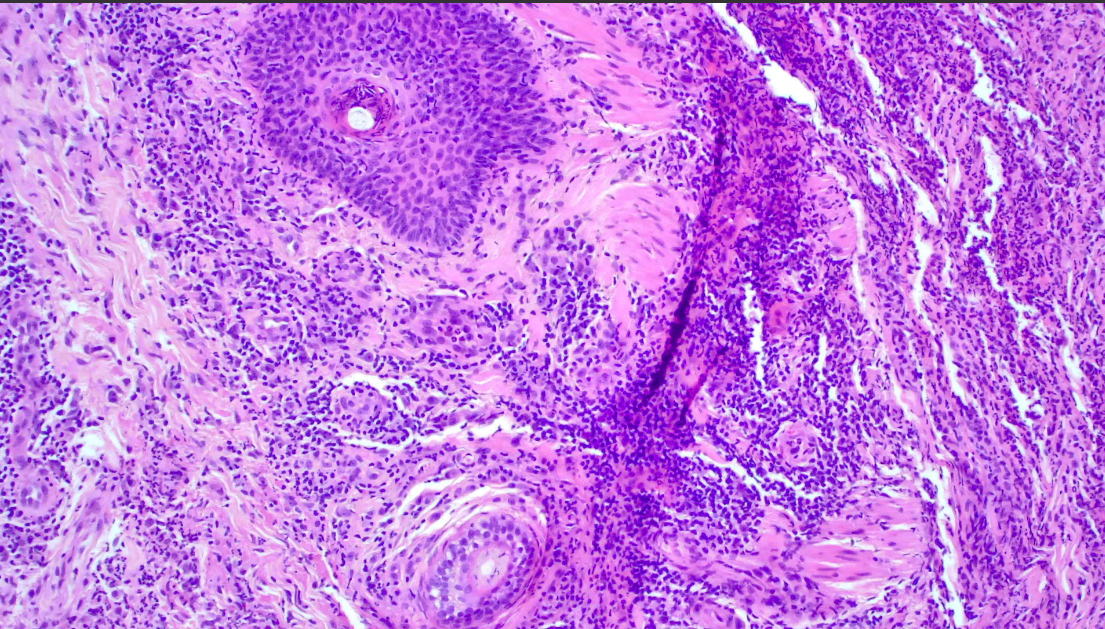

Discussion: LCV is an immune complex-mediated vasculitis of the dermal arterioles, capillaries, and venules in which neutrophils infiltrate vessel walls and surrounding structures. Annually, the incidence of biopsy-confirmed LCV is about 45 per million people. About 10% of vasculitis are drug-induced and cutaneous manifestation onset occurs 1-3 weeks after drug initiation. Antibiotics are one of the biggest culprits of secondary LCV, with beta-lactams being the most common. Recently, researchers have reported the induction of LCV from Oxacillin, ceftriaxone, and cefazolin use. Clindamycin-induced LCV is uncommon as there appears to be a singular reported case of clindamycin-induced leukocytoclastic angiitis within the last 50 years. As clindamycin is frequently used in an inpatient setting to cover for MRSA infections, awareness of LCV in the setting of clindamycin is valuable for guiding patient care.The severity and progression of LCV are often assessed using cutaneous biopsy findings. In early stages, the histopathological presentation of LCV may include focal damage of capillary vessel walls as well as mild granulocytic infiltrates. As part of the work-up for patients with suspected LCV, a cutaneous biopsy should always be performed as it will give insight into disease prognosis and systemic complication risk.